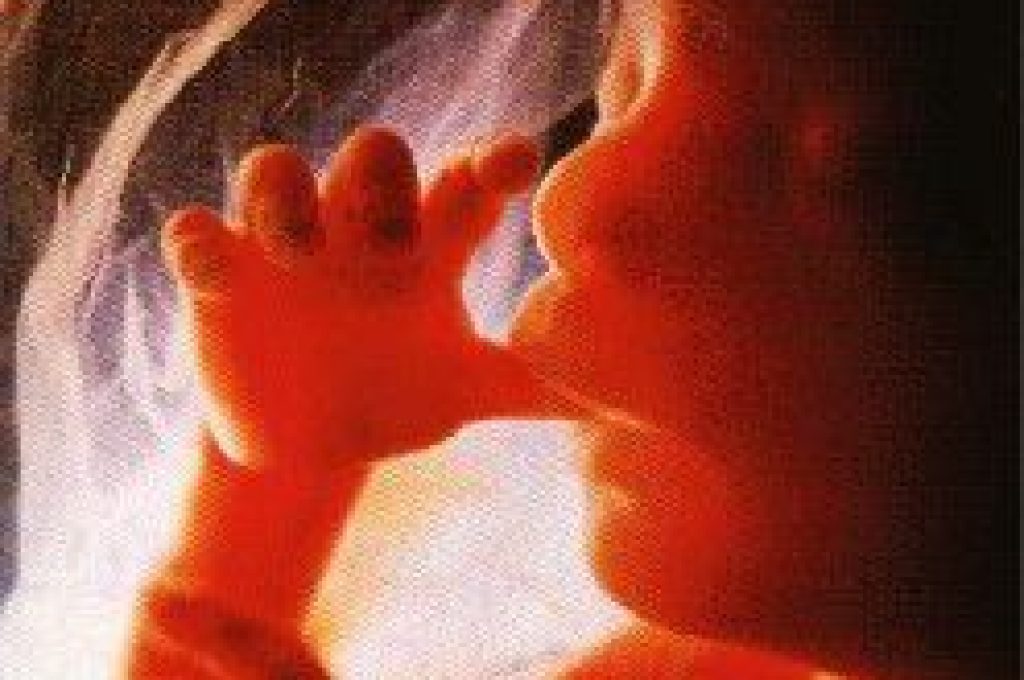

La scoperta da parte dei Nas e Magistratura di un ginecologo ospedaliero che particava aborti fuori dei termini di legge ed il fatto che, da quel che sembra dalle dichiarazioni rilasciate, i responsabili sanitari della Usl fossero all’oscuro di tutto fino all’avviso di conclusioni indagini, ha dato occasione alla consigliera regionale umbra dell’Udc di salire sul cavallo da battaglia del suo partito.

Sandra Monacelli ha rivolto un’interpellanza alla Giunta regionale, nella quale chiede ”Quali urgenti provvedimenti adottare sul caso dell’inchiesta dei Nas denominata ”Erode", riguardante la pratica di presunti aborti fuorilegge all’interno di una struttura pubblica, sia in ordine ai fatti che coinvolgono personale e struttura sanitaria pubblica, che in ordine alla verifica della corretta attuazione della legge 194 in tutte le sue parti”.

”Qualora i fatti descritti fossero accertati – prosegue – si aprirebbero inquietanti dubbi circa la presunta diminuzione di interruzione volontaria della gravidanza, come asserito dalla Direzione regionale alla Sanità dell’Umbria, che sembrerebbe non possedere dati certi sulla diminuzione degli aborti clandestini tradizionali ne’ sulla vendita di migliaia di confezioni di pillola del giorno dopo, la cui assunzione in non pochi casi determina la distruzione di precocissimi embrioni, cioe’ la realizzazione di migliaia di aborti occulti e quindi clandestini".

Sandra Monacelli ha rivolto un’interpellanza alla Giunta regionale, nella quale chiede ”Quali urgenti provvedimenti adottare sul caso dell’inchiesta dei Nas denominata ”Erode", riguardante la pratica di presunti aborti fuorilegge all’interno di una struttura pubblica, sia in ordine ai fatti che coinvolgono personale e struttura sanitaria pubblica, che in ordine alla verifica della corretta attuazione della legge 194 in tutte le sue parti”.

”Qualora i fatti descritti fossero accertati – prosegue – si aprirebbero inquietanti dubbi circa la presunta diminuzione di interruzione volontaria della gravidanza, come asserito dalla Direzione regionale alla Sanità dell’Umbria, che sembrerebbe non possedere dati certi sulla diminuzione degli aborti clandestini tradizionali ne’ sulla vendita di migliaia di confezioni di pillola del giorno dopo, la cui assunzione in non pochi casi determina la distruzione di precocissimi embrioni, cioe’ la realizzazione di migliaia di aborti occulti e quindi clandestini".